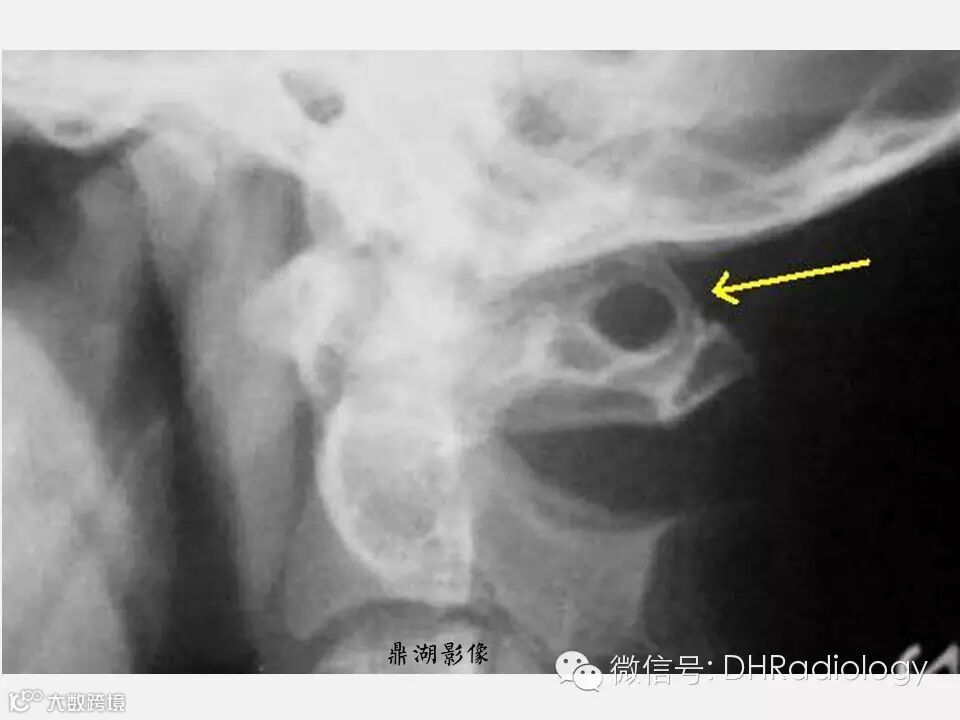

【聚沙成塔】教你一个有意思的变异——寰椎沟环畸形

这是什么呢?

有什么临床意义?